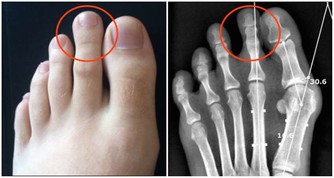

不同的情緒對應著不同的身體疾病。比如恐懼、焦慮會導致腹部疼痛;批評、內疚引發關節炎;

壓抑導致哮喘;經常憤怒的人容易有口臭,還愛發生膿腫;恐懼會引發暈車和痛經。